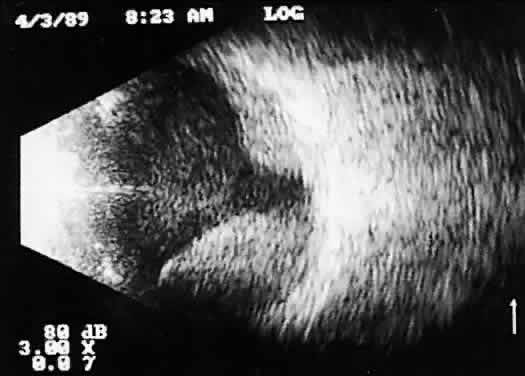

During contact B-scan imaging, each quadrant of the globe is scanned systematically from probe positions that avoid, if possible, any passage of the examining or returning sound through the artifact-inducing lens system (Fig. 8). For the beginner, practice with clear media patients, such as those with total or partial retinal detachment, is essential (Fig. 9). The ultrasonically derived vitreoretinal drawing can then be compared to standard optical examinations. As experience increases, similar but more difficult cases can be attempted. Specifically, B-scan examination of diabetic patients with traction retinal detachments and clear media should be attempted and compared to visually controlled drawings. These self-testing exercises, especially in complex cases, provide the examiner a feeling for his or her level of competence and reliability in 3D thinking. Opaque media cases can then be approached with greater confidence and diagnostic accuracy.

Fig. 9. Contact B-scan: total retinal detachment, anteroposterior view. Characteristic V-shaped appearance with attachment to the optic nerve head.